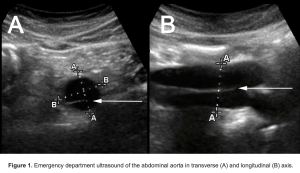

Ultrasoundoftheweek.com hade nyligen ett case med en aortadissektion och visar snyggt hur det kan se ut och sammanfattar hur man ska titta med ultraljudet.

Så kan vi använda ultraljud istället för DT när vi misstänker aortadissektion? Nej! Inte än iaf. Det finns knappt några bra studier gjorda i ämnet utan mest case reports. Den enda vettiga studie jag hittade undersökte hur bra ultraljud är vid typ A dissektion och kom fram till 88% sensitivitet och 94% specificitet. Om man kombinerade ultraljud med the aortic dissection detection (ADD) risk score så blev sensitivitet 96% och specificitet 98% vilket ju låter väldigt lovande men studien var bara på 281 personer varav 50 hade aortadissektion. Författarna själva tyckte heller inte att man kunde förlita sig på enbart ultraljud (ens i kombination med ADD risk score) för att diagnostisera aortadissektion.

Scanna så många aortor du kommer åt, för erfarenhetens skull, men räkna inte med att du kan utesluta aortadissektion med ultraljud. Hittar du en dissektion så kan du vara ganska säker på att det verkligen finns en dissektion men thoraxkirurgerna vill med största sannolikhet ha en DT innan de opererar ändå.